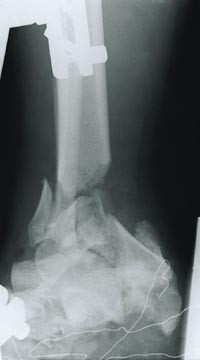

En 26 år gammel, mannlig bygningsarbeider arbeidet med fjerning av et sikringsrekkverk i 11 etasje, da han falt 28 meter fra et bygningsstillas mot en betongflate. Horisontal avstand til treffpunkt fra stillaset ble ikke målt. Han skal ifølge øyenvitner ha falt med hodet først, men roterte i løpet av det frie fallet og landet på beina, sannsynligvis med en viss grad av rotasjon mot bakken. Sveisemasken han hadde på, ble knust i fallet. Han ble umiddelbart bevisstløs, men pustet spontant, og han ble raskt brakt til sykehus, intubert og tilkoblet respirator. Ved fallet hadde han pådratt seg følgende skader: Kranie-basisfraktur, frontal fraktur, små kontusjoner i høyre hemisfære og intra- og subduralt hematom, bilaterale costafrakturer og bilaterale lungekontusjoner med antydning til pneumothorax, moderat væskeansamling rundt milten og foran urinblæren, kompresjonsfraktur av L2 med dislokert tverrtagg, liten corpusfraktur av L4, sacrumfraktur på høyre side over mot venstre og fraktur gjennom nerveforamina, høyresidige femurfrakturer av collum og distale del, høyresidig patellafraktur, bilateral ankelfraktur med betydelig knusning av distale venstre tibia og venstre calcaneus samt avsprengt venstre talus og (fig 1) fraktur av venstre humerus.